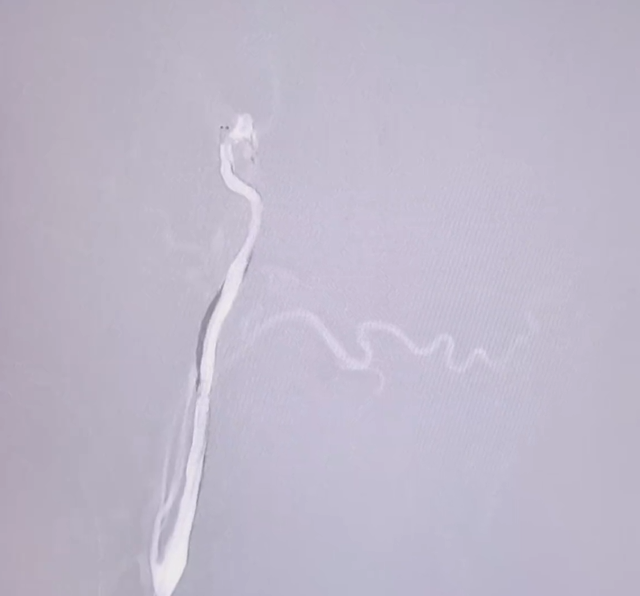

DSA示右侧颈内动脉次全闭塞

术中采用"先清淤、后修路、再架桥"的阶梯式策略:

(1) 精准通路建立,分阶段“清淤”, 球囊辅助通过+机械抽吸,成功捕获颈动脉两条暗红色血栓(4cm及1cm)。

暗红色血栓(4cm及1cm)

(2) 阶梯式血管成形:"球囊序贯扩张"修复通路。复查造影示:前向血流明显改善,但仍有狭窄。

球囊序贯扩张

(3) 精准支架植入:为血管架起"长期保护桥",复查造影示:支架贴壁良好,管腔通畅,无残余狭窄。

从穿刺到血管完全再通,团队以最少的器械交换次数完成了这一急救操作,最大程度降低了手术相关并发症风险。